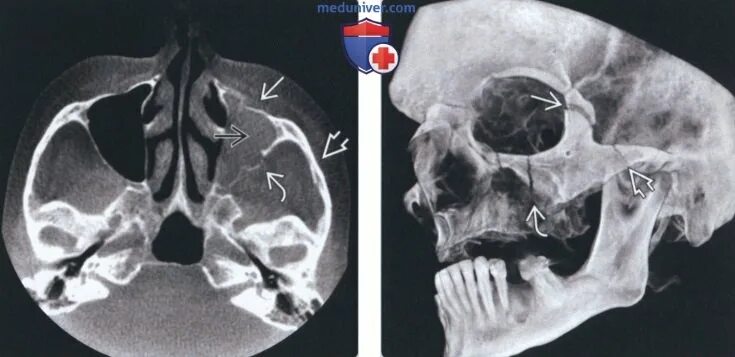

Нарушение пневматизации верхнечелюстных